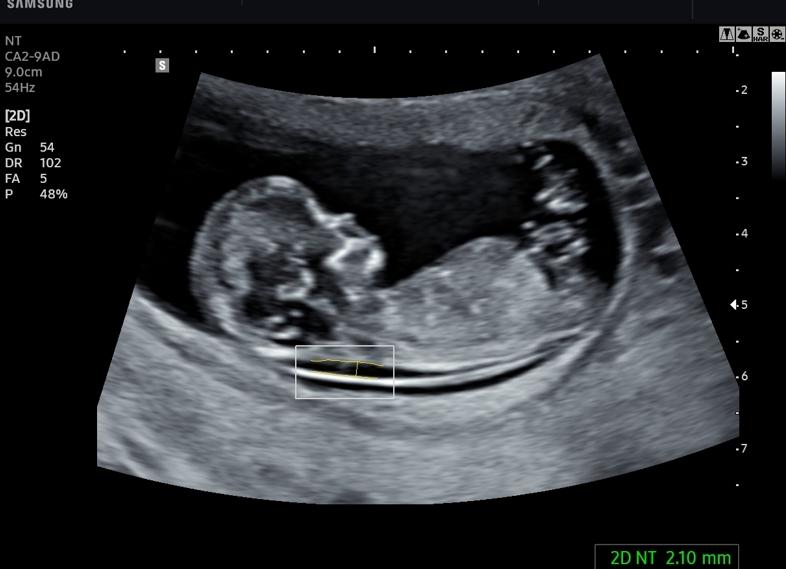

При проведении скрининг УЗИ в 12 недель беременности особое внимание уделяется головному мозгу, который к данному сроку должен иметь два полушария. Кроме того процедура позволяет врачу проанализировать воротниковую область и установить ее толщину, которая показывает, есть ли риск возникновения болезни Дауна. Если показатели толщины не соответствуют норме (в пределах от 2 до 3 мм), а превышают ее, то врач будет подозревать у плода наличие хромосомных аномалий. В этом случае усиливается контроль над состоянием будущей мамы и тем, как развивается ребенок, и повторно делается скрининг УЗИ через 2 недели.

• Толщина воротниковой зоны (ТВР) – должен быть в границах 0,71–2,5 мм. Показатель 2,7 считается критическим, и указывает на присутствие синдрома Дауна.

Снимок УЗИ на 12 неделях позволяет оценить ТВП – один из важных показателей для выявления синдрома Дауна.

ТВП (толщина воротникового пространства) в 12 недель при отсутствии патологий не выходит за границы диапазона 0,7-2,5 мм. Если у малыша этот параметр превышен незначительно, будущей маме могут порекомендовать пройти УЗИ повторно через неделю. Если ТВП существенно превышает верхние границы нормы, потребуется дополнительное обследование, риски родить больного малыша повышаются. Речь идет о превышении от 3,0 мм и выше.

Есть несколько показателей, которые исследует врач. Самый важный — ТВП. Толщина воротничкового пространства, это толщина мягких тканей вокруг шеи. В норме считается показатель не более 3 мм. Если показатель повышен, это может свидетельствовать о возможных патологиях.

Для определения отклонений требуется эти две величины. Измерение ТВП имеет смысл при размерах КТР 45–85 мм, поэтому важно проводить скрининг не раньше 11 и не позже 13 недели.